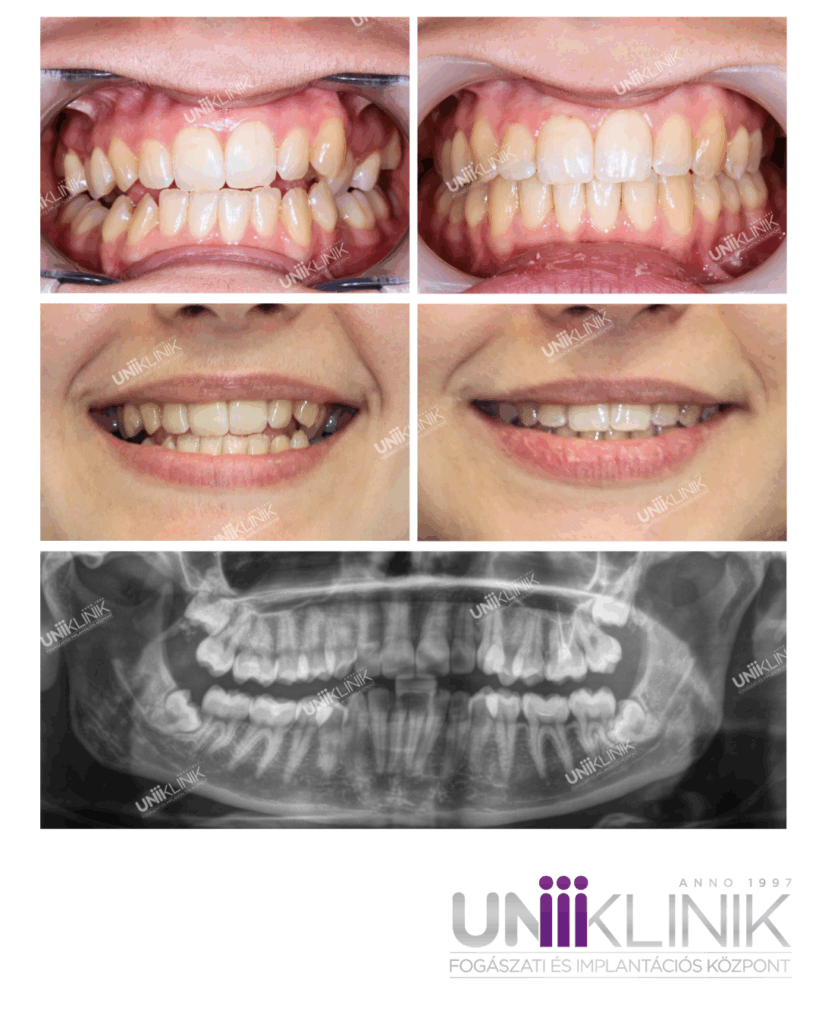

Ektópiás Szemfog Fogszabályozása